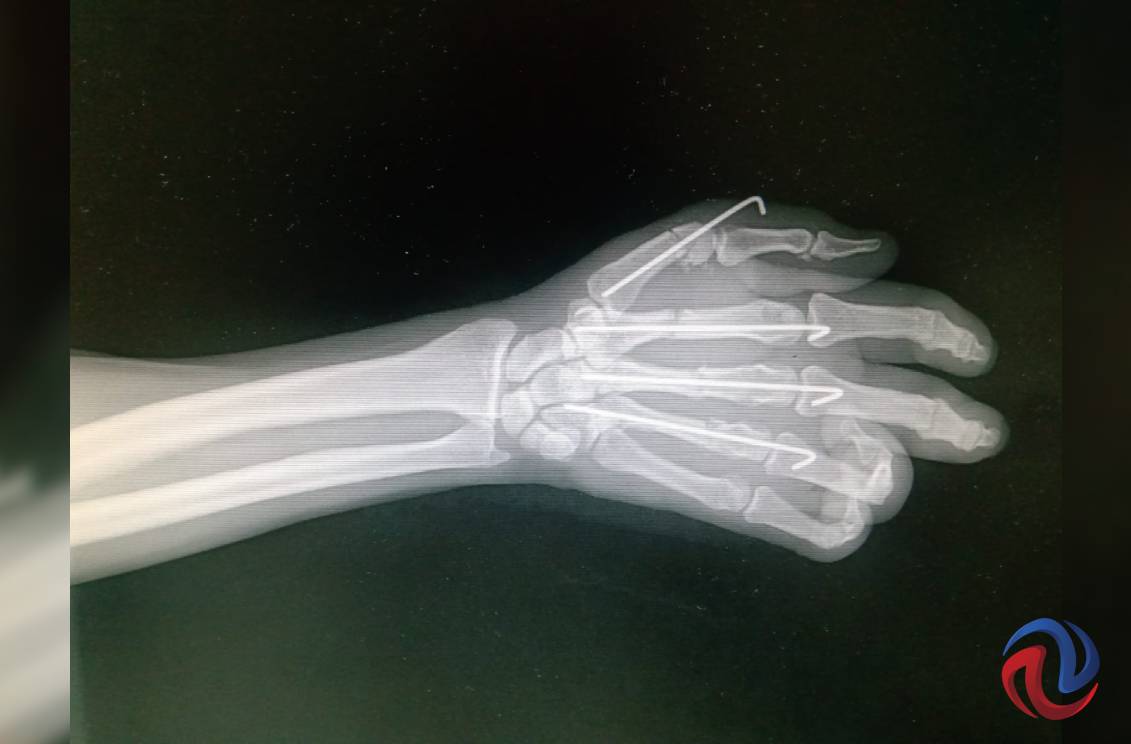

TIJUANA BC 30 DE JUNIO DE 2021 (AFN).- El pasado 15 de abril Horlando estaba a punto de concluir su trabajo, donde operaba una sierra para cortar metal, cuando en un movimiento inesperado el equipo alcanzó su mano derecha provocándole una herida tan grave que según el diagnóstico inicial le haría perder la extremidad. Hoy casi tres meses después no solo la conservó, sino que avanza rápidamente en la recuperación gracias a médicos del Instituto Mexicano del Seguro Social.

“Dos días después del accidente, el sábado, me llevaron a quirófano. Fue una operación muy larga, más de cuatro horas; me pusieron cinco clavos y lograron salvar mi mano”, recuerdó Horlando. Johana Ocampo Villalobos, traumatóloga ortopedista del IMSS, dijo que se logró la reconstrucción ósea y la reparación vascular, nerviosa y de tendones para salvar la extremidad.

Después de ese momento, y a la fecha, Horlando ha sido sometido a dos nuevas cirugías, una de ellas para realizar un exitoso injerto de piel. El tratamiento recibido ha dado pie a una recuperación notable, que permitió el retiro de los clavos dos semanas antes de lo programado.